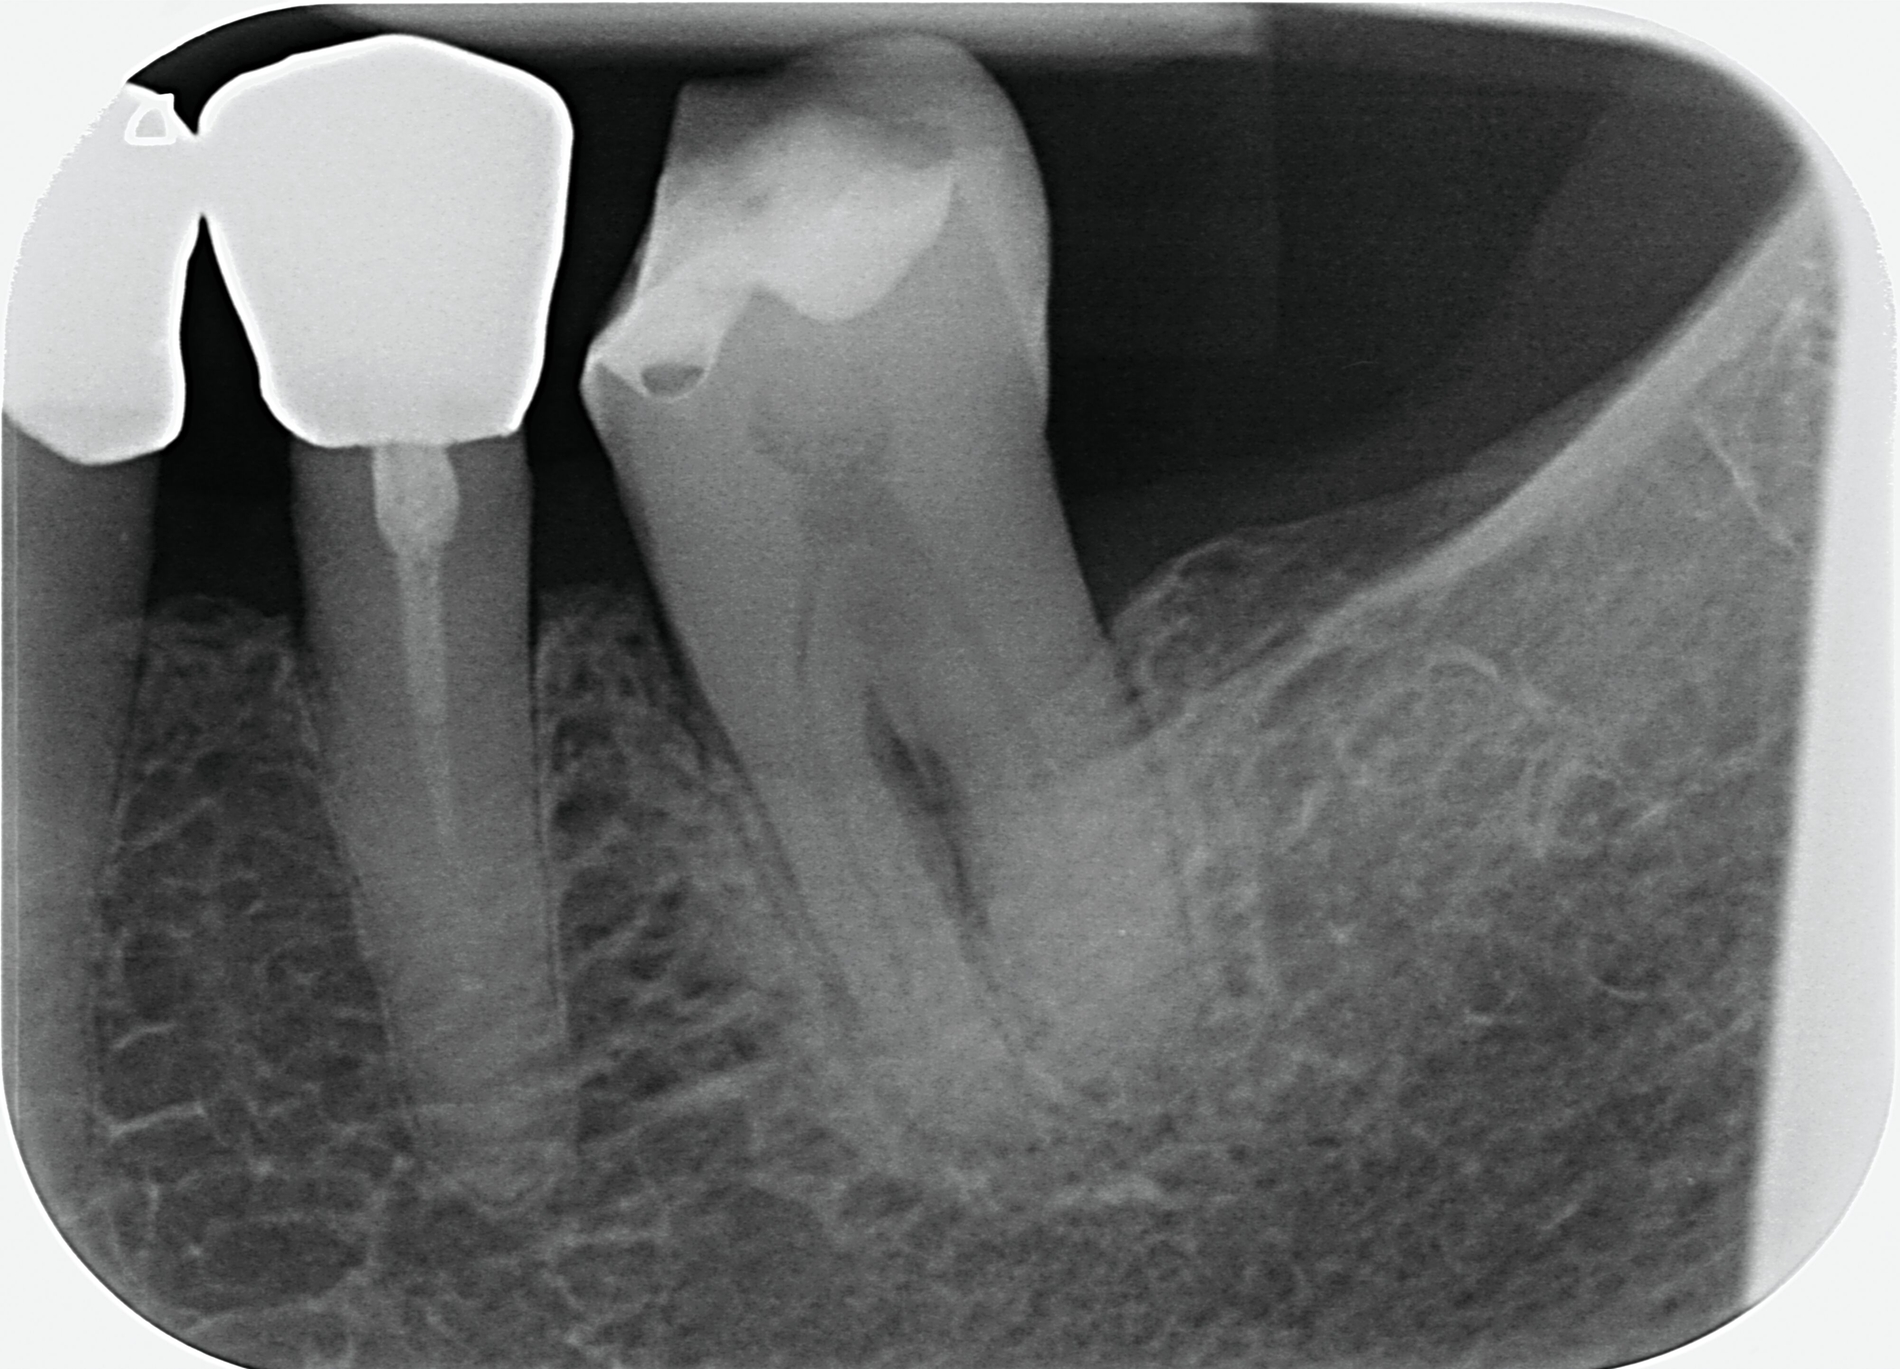

Da anhand eines Zahnfilms festgestellt worden war, dass der Zahn 31 – vermutlich aufgrund einer Paro-Endo-Läsion – eine apikale Aufhellung zeigte, war bereits die Extraktion mit anschließender Umarbeitung und adhäsiver Wiedereingliederung des extrahierten Zahnes als Option angesprochen worden. Kurz vor dem vereinbarten Eingriff meldete sich die Patientin telefonisch, um sich zu erkundigen, ob sie den Termin denn überhaupt noch benötige, da der betroffene, gelockerte Zahn 31 in der Unterkieferfront beim Essen von selbst herausgefallen sei und sie ihn bereits entsorgt habe. Schmerzen, eine Schwellung oder Nachblutungen verneinte die Patientin. Sie wurde gebeten, den vereinbarten Termin am Folgetag dennoch wahrzunehmen, mindestens zur Kontrolle der Wunde, gegebenenfalls zur Planung der Weiterversorgung (Abbildungen 5 und 6).